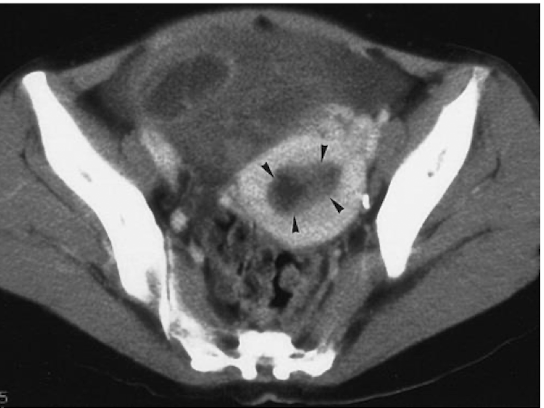

What is this

Bladder Cancer